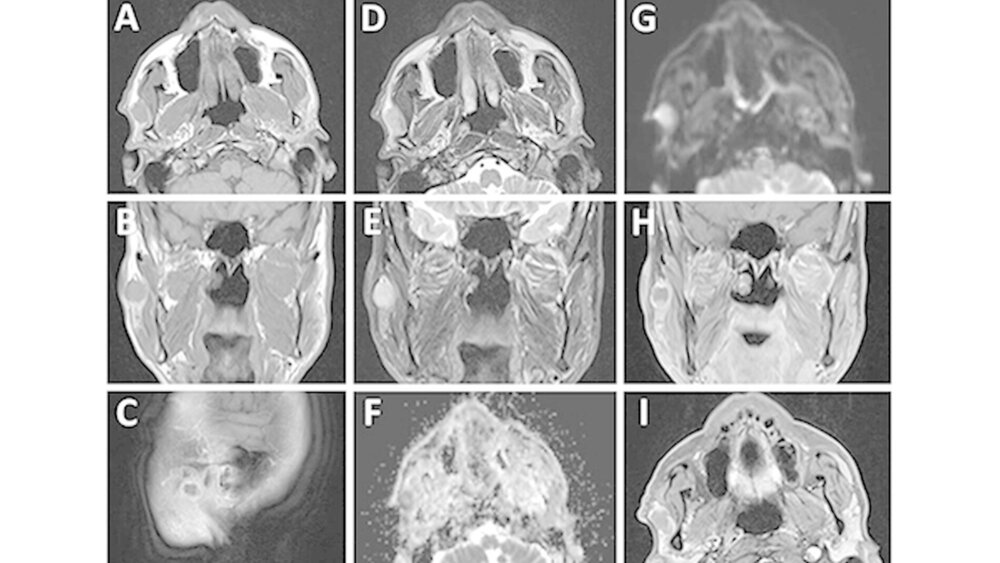

Klinisch wurden keine sensomotorischen Ausfälle im Gesichtsbereich festgestellt. Palpatorisch fand sich eine haselnussgroße, nicht schmerzhafte, bedingt verschiebliche Raumforderung im Bereich der rechten Gl. parotis. Eine B-Symptomatik wurde vom Patienten verneint. Die manuell provozierte Salivation aus dem rechten Stenon-Gang war spontan klar flüssig. Sonografisch zeigte sich ein kreisrunder homogener, im zentralen Drüsengewebe integrierter Tumor mit einem Durchmesser von etwa 18 mm. Zervikal vergrößerte Lymphknoten waren nicht darstellbar. Zur weiteren Abklärung eines möglichen Zystadenoms erfolgte die Anfertigung eines Hals-MRT mit Kontrastmittel. Das angefertigte MRT ergab eine scharf begrenzte zentrale Raumforderung der rechten Gl. parotis mit einer Ausdehnung von 18 mm x 10 mm, die sich zum angrenzenden Muskelgewebe in der T1-Gewichtung hypointens (Abbildung 1A bis 1C) sowie in der T2-Gewichtung leicht hyperintens (Abbildung 1D und 1E) darstellte.

Der ADC-Wert (apparent diffusion coefficient-Wert) war deutlich vermindert (Abbildung 1F und 1G). Die Kontrastmittel gestützten Sequenzen wiesen lediglich eine dezente randständige Anreicherung auf (Abbildung 1h und 1l). Pathologisch veränderte Lymphknoten waren nicht nachweisbar. Im MRT wurde zunächst der Verdacht eines Warthin-Tumors geäußert. Nach Resektion der tumorösen Raumforderung unter Schonung des Plexus parotideus ergab das histologische Ergebnis ein in sano reseziertes, stark proliferierendes, maximal 2,5 cm großes, myoepitheliales Karzinom von insgesamt spindelzellig-mesenchymalem Aspekt (Abbildung 2a) mit einem minimalen Sicherheitsabstand von 0,1 mm (TNM-Klassifikation (8. Auflage): pT2, G3, R0). Immunhistochemisch wurde eine intensive Expression von Zytokeratin 18 (CK18; Abbildung 2b) sowie eine intensive Kernmarkierung mit Ki-67 nachgewiesen (Abbildung 2c). Zusätzlich fand sich eine fokale Expression von glattmuskulärem Aktin (Abbildung 2d) und Desmin.